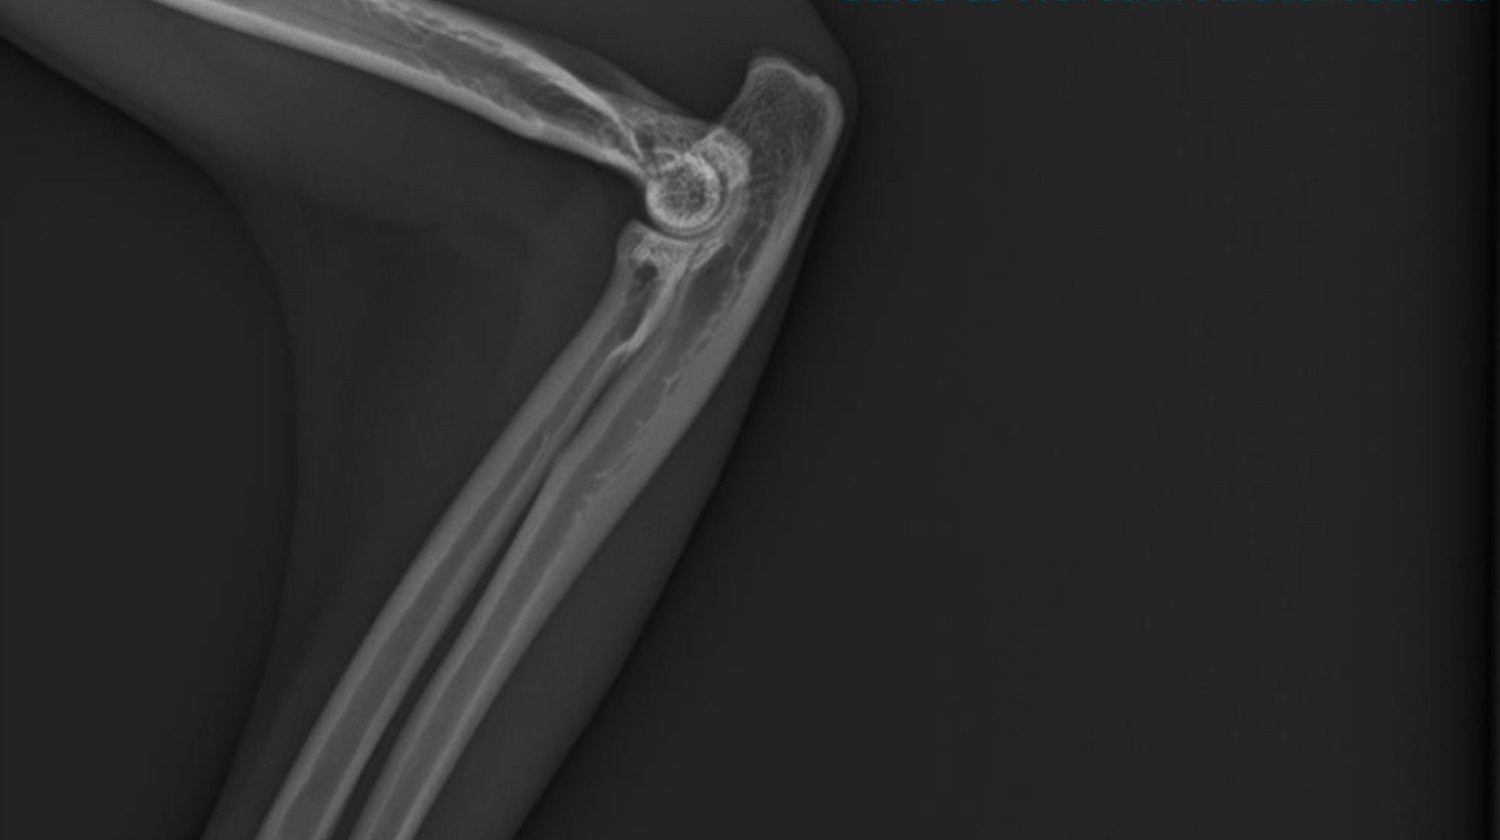

Notre famille vient de vivre une tragédie déchirante : notre chat bien-aimé a été renversé par une voiture. Sa patte est gravement cassée, elle souffre énormément et les vétérinaires disent que seule une intervention chirurgicale immédiate et salvatrice peut lui donner une chance de survivre. Chaque minute d'attente diminue ses chances.

Une immense tragédie est arrivée à notre famille : notre chat adoré a été renversé par une voiture. Dans l'accident, sa patte a été gravement cassée, il souffre énormément, et les vétérinaires disent que seule une chirurgie immédiate et salvatrice peut lui donner une chance de survie. Chaque minute d'attente diminue ses chances de survie.